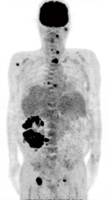

透析患者さんには腎がんの発生が多いというデータがあります。しかし、CTや超音波検査などでも、発見が困難なことが少なくありません。このプロジェクトは透析患者さんの腎がん早期発見を目的としてFDG-PETの有用性を調査するものです。

プロジェクトは現在進行中です。

透析患者さんでPET検査を受けてくださる方を募集しています。

131I-MIBGは、神経堤(neural crest)が発生母地となる神経内分泌腫瘍である褐色細胞腫、傍神経節腫、神経芽細胞腫などに集積するため、このことを利用して、131Iの放出するβ線を用いて癌細胞の内部より選択的に照射を行うRI内照射治療が可能です。褐色細胞腫の約10%は稀ではありますが悪性化することがあり、全身に転移します。この様な症例には、現在なかなか有効な治療法がありませんが、131I-MIBG治療の適応になることがあります。

群馬大学附属病院では、2004年より当院IRBの承認を受けて、年間約10-15症例の悪性褐色細胞腫・傍神経節腫を対象として本治療を行なっています。患者さんは東北、首都圏を中心とした関東全域など広く東日本全域より来院されます。予め、担当医より紹介状の送付を頂き、適応に関して評価を行い、その後患者様の外来受診、検査入院(約5日間)、治療入院(約10日間)という流れで診療が進行します。131I-MIBGは、本邦では未承認薬であるため、ポーランドより個人輸入しています。

現在FDG-PET画像において癌への異常集積を評価する指標としては、SUVmaxが広く使われています。簡便な指標ではあるものの、病巣全体の糖代謝を反映していない面もあり、他の指標として病巣への異常集積の見られる容積の評価が重要となってきています。Metabolic volumeは、PETVCAR (Volume Computer Assisted Reading)による、コンピュータ支援ボリューム解析により計測されます。本研究では、2007年より2012年までに、群馬大学附属病院でFDG-PET検査を行われた肺癌の症例のPET画像を対象に、Metabolic volumeと肺癌の予後との関係をレトロスペクティブに解析を行っています。